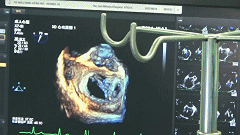

完全在超声引导下完成二尖瓣夹的定位、瓣叶抓取和二尖瓣夹的释放

三维超声确认夹合位置理想